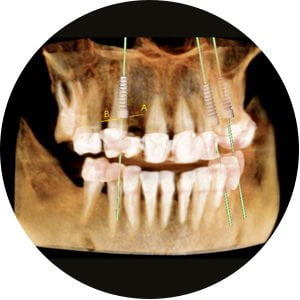

Following the CBCT scan, the 3D image reconstruction will be used to plan the correct surgical placement of your implant/s and can be used as well for the production of a surgical guide printing for a more accurate implant position as per your digital plan.